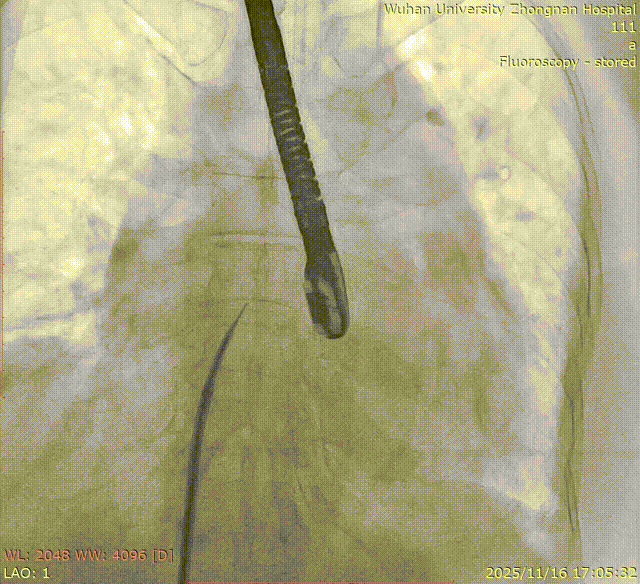

Left Atrial Appendage Closure (LAAC):The delivery system was successfully advanced into the left atrium. Precise measurements of the LAA orifice and depth were taken under multi-angle TEE and DSA guidance. Given the LAA's large orifice (nearly 34mm), conical cauliflower shape, and shallow usable depth, a LACBES2434 occluder was selected. Using the "extreme coin technique," the closure was successfully achieved.

DSA